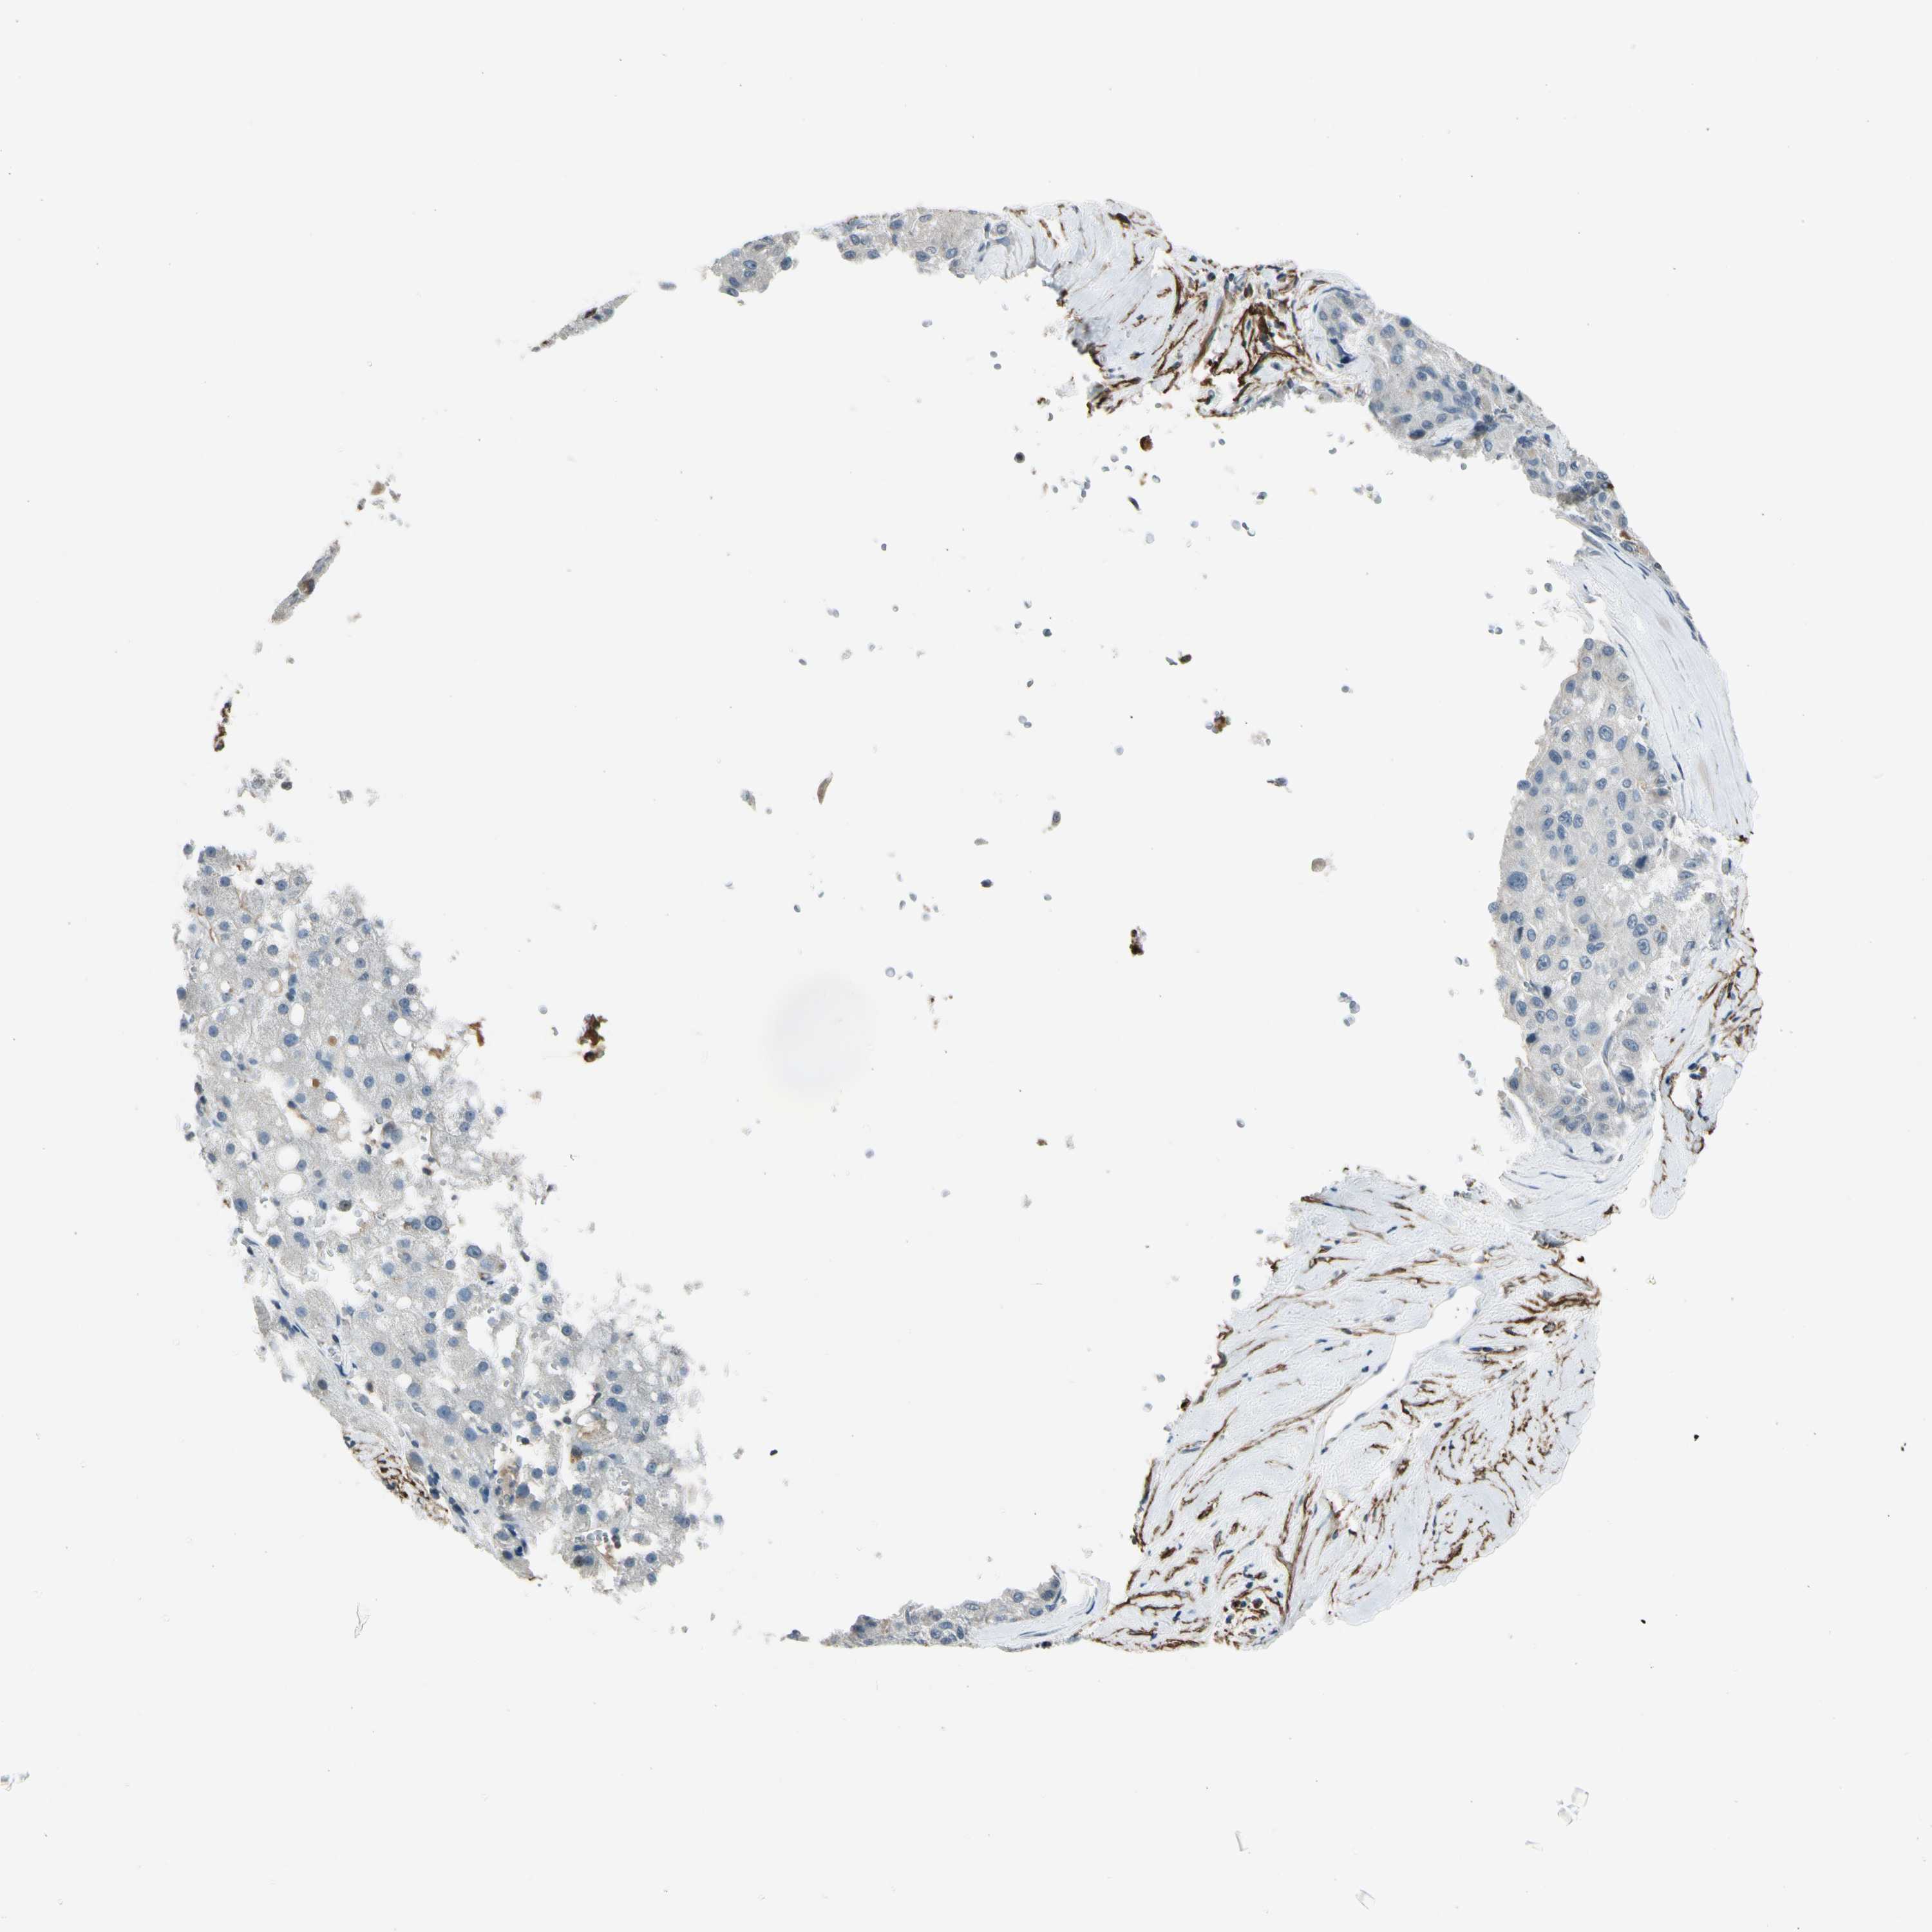

LIVER CANCER - Protein expressioni

A mouse-over function shows sample information and annotation data. Click on an image to view it in a full screen mode. Samples can be filtered based on level of antibody staining by selecting one or several of the following categories: high, medium, low and not detected. The assay and annotation is described here.

Note that samples used for immunohistochemistry by the Human Protein Atlas do not correspond to samples in the TCGA dataset.

Antibody stainingi

Antibody staining in the annotated cell types in the current human tissue is reported as not detected, low, medium, or high, based on conventional immunohistochemistry profiling in selected tissues. This score is based on the combination of the staining intensity and fraction of stained cells.

Each image is clickable and will lead to virtual microscopy that enables deeper exploration of all samples and also displays staining intensity scores, fraction scores and subcellular localization as well as patient and tissue information for each sample.

Antibody HPA007534

Antibody CAB008376

Staining

High

Medium

Low

Not detected

Intensity

Strong

Moderate

Weak

Negative

Quantity

>75%

75%-25%

<25%

None

Location

Nuclear

Cytoplasmic/membranous

Cytoplasmic/membranous,nuclear

Cholangiocarcinoma

Carcinoma, Hepatocellular, NOS